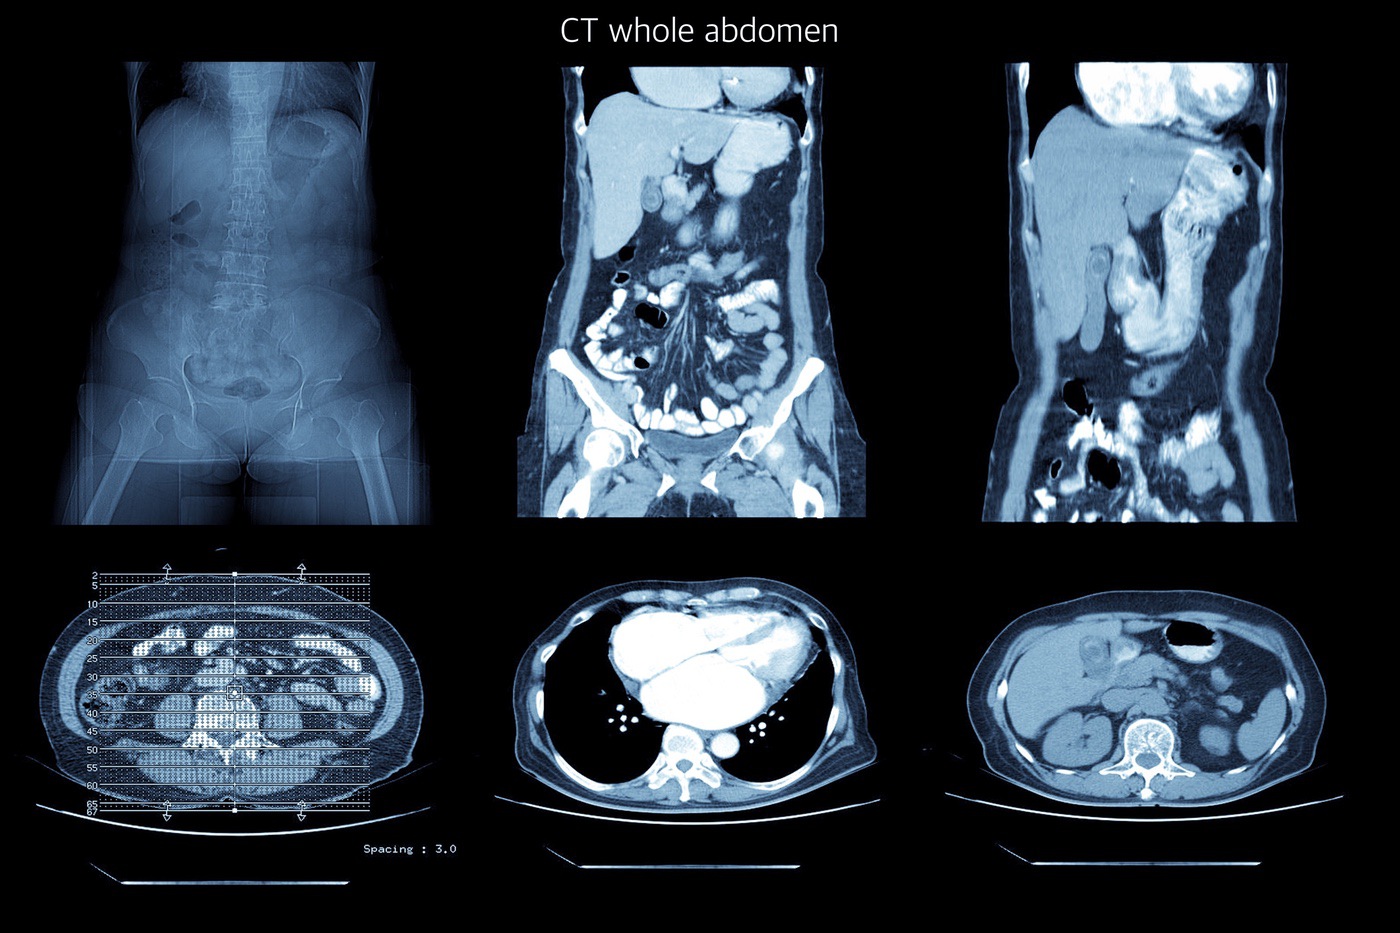

Full Body Ct Scan X Ray

mavink.com

mavink.com

CT Scan: What It Is, Types, Purpose, Procedure & Results

my.clevelandclinic.org

my.clevelandclinic.org

CT Scan - Definition, Uses And Procedure

healthtian.com

healthtian.com

ct scan cat procedure technique definition body machines use ray uses share